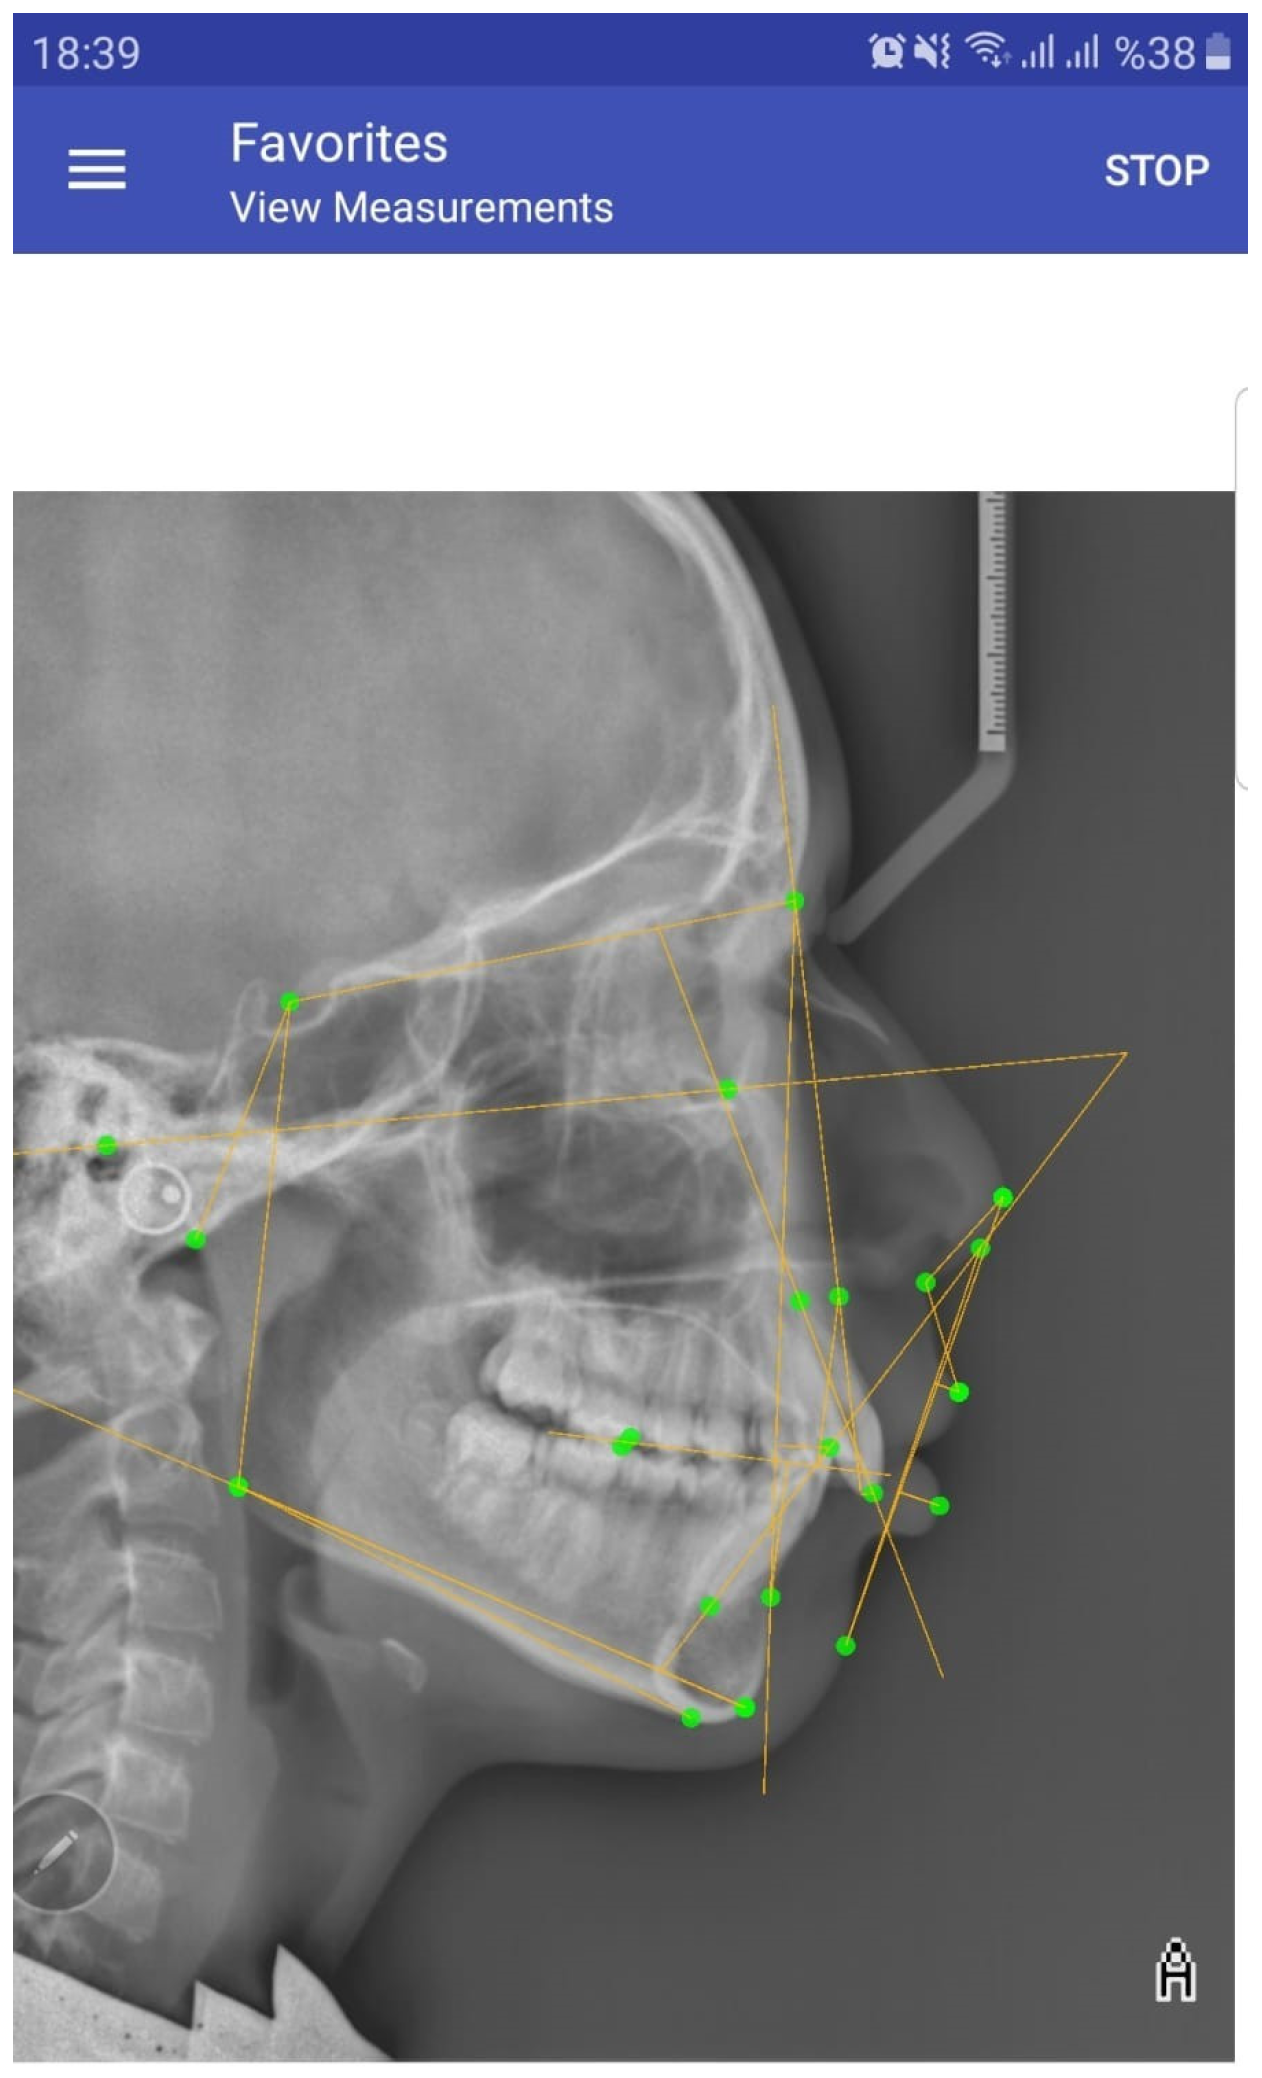

- OneCeph Analysis Application